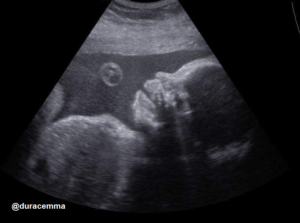

Mi a 28-29. hét környékén mentünk baba mozira (Hepinet), mert akkor már biztosan látszik, hogy milyen nemű is lesz a gyermek, szóval még éppen elég időnk is lesz az előkészületekre.

Kislány!!! Juhuuuuuu!!!!